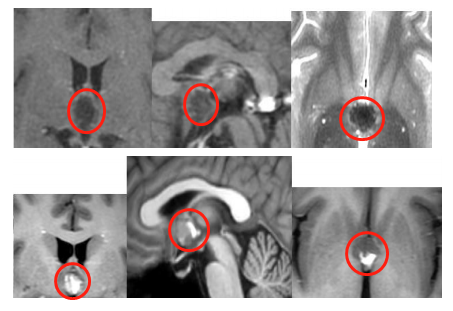

西藏的景色美不胜收,然而回到家后浩然开始频繁出现头痛、头晕的情况。起初以为是离开高原后的“醉氧”反应,休息几天就好了,但是没想到头痛头晕的症状一直没有好转,甚至在旅游回家两个月后依然存在,并且和普通头晕头痛不同,浩然头痛头晕还伴着坐下站立的一瞬间,头后部及尾椎部同步疼痛,甚至有时候站立不稳。就医头颅核磁检查后考虑第三脑室病变,疑似海绵状血管瘤,约14×13×10mm大小。

保守治疗2个月后,浩然的症状并没有得到缓解,甚至有了加重的趋势,头昏脑胀,头晕,没精神。去医院核磁复查后,较之前核磁结果范围增大、信号混杂,大小约16×14×14mm,仅仅2个月的时间,肿瘤发展就如此迅速,并且症状加重的原因还考虑是海绵状血管瘤伴出血。海绵状血管瘤一旦出血,再次出血的几率就会增加,间隔时间也会缩短,相应的症状也会加重。这次医生没有让浩然继续保守治疗,而是建议手术治疗。